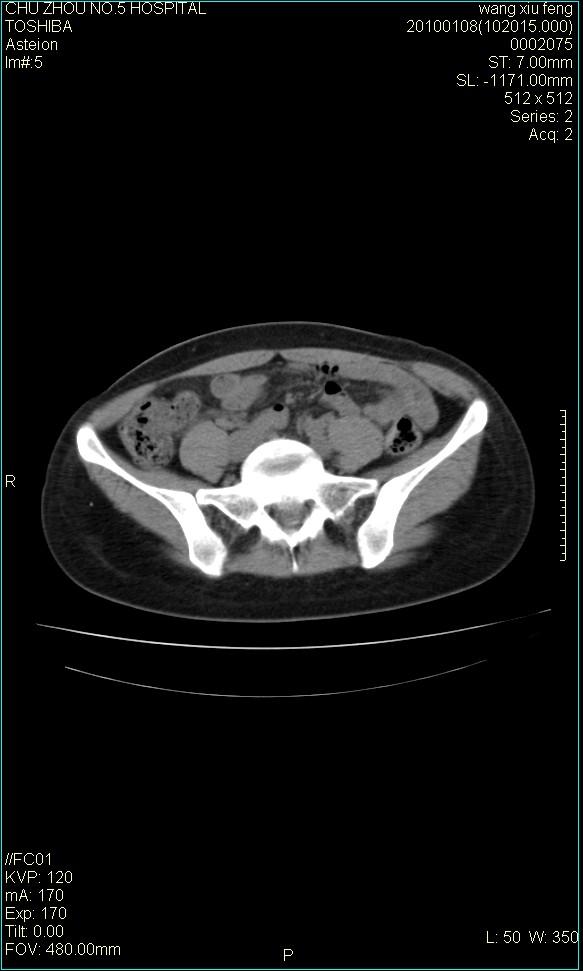

f-41,左乳腺ca术后4年,b超示:子宫右上方囊性包块约5.5*3.4cm,前日行胸部ct平扫未见明显异常。

考虑右侧卵巢囊腺瘤?

右侧卵巢囊肿或小囊腺瘤。

考虑肠系膜囊肿可能性大

考虑右侧卵巢囊腺瘤?建议增强!

考虑右侧卵巢囊腺瘤。

考虑右侧卵巢囊性占位性病变(囊肿?囊腺瘤?)。